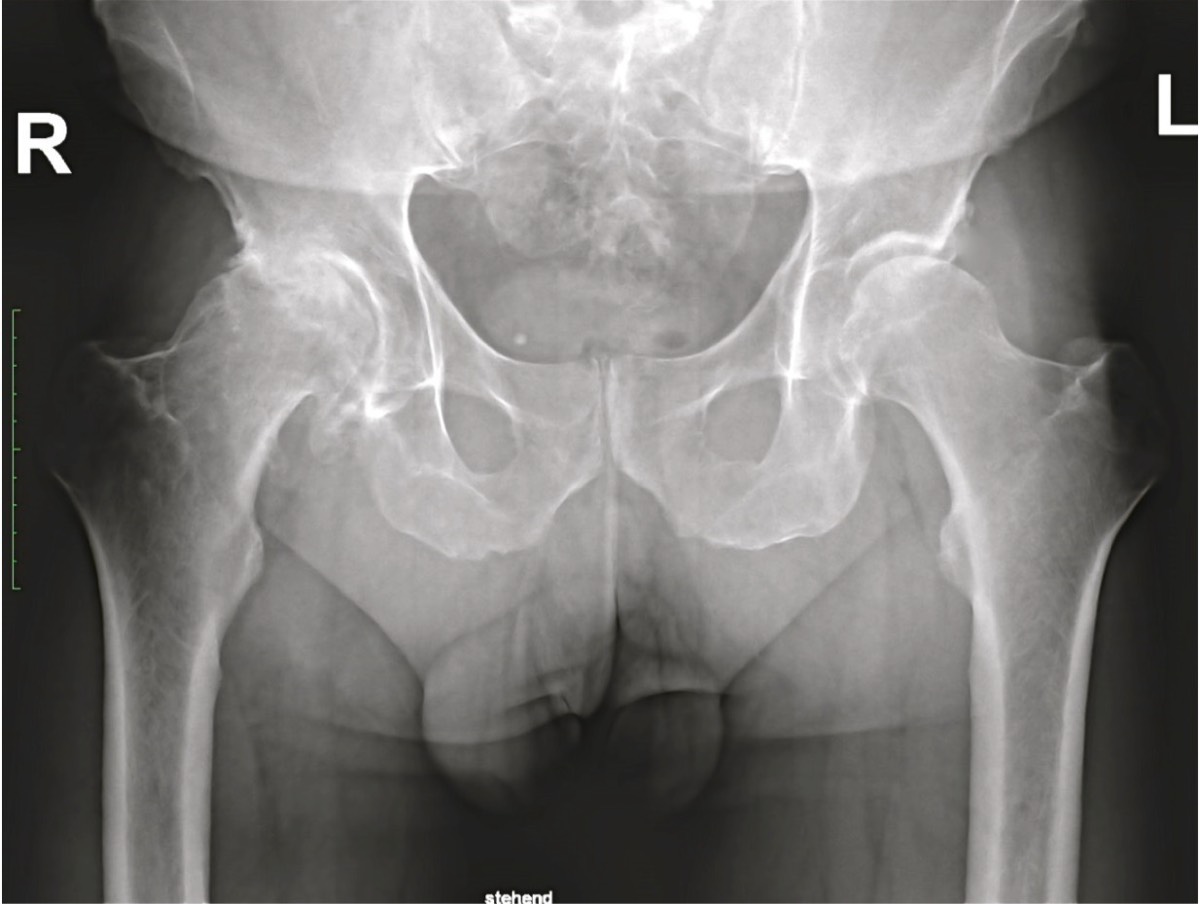

Im Röntgenbild ist der Gelenkknorpel nicht sichtbar. Dadurch ist zwischen Pfanne und Kopf ein deutlicher Abstand, der Gelenkspalt sichtbar. Bei der Arthrose ist dieser Spalt verschmälert oder gar ganz fehlend. Für die Diagnose der Arthrose stellt somit das konventionelle Röntgenbild noch immer eine unübertroffene Hilfe dar.